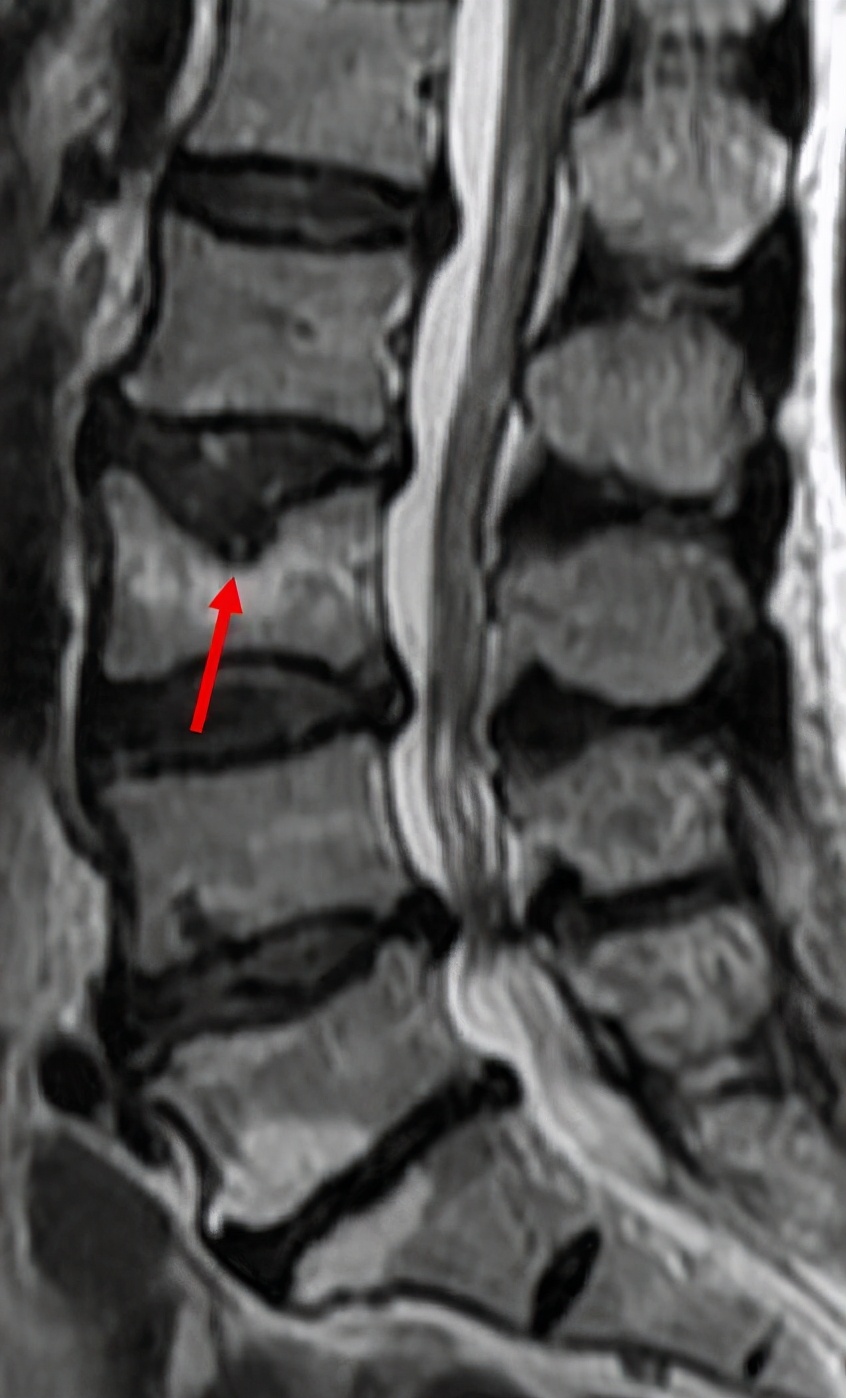

4、Schmorl 结节: 髓核经上下终板软骨的裂隙进入椎体松质骨内,大部分患者无肿胀,不需要手术治疗。

腰椎MRI显示Schmorl 结节